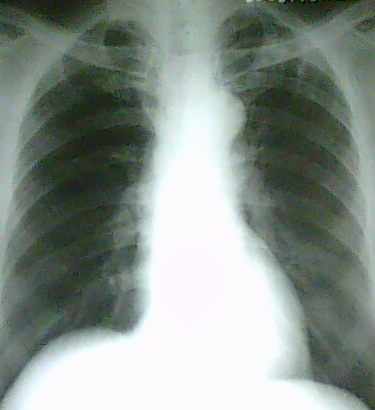

男.75y。结肠ca术后5年常规胸片。

(大家说的都没错。因为手机照的,所以看上去片子不很清楚。从原片看病变处的肋骨密度似乎不太均匀,有点不放心,所以后来透视了一下,是陈旧结核病灶与肋骨的重叠造成的假象。所以x线平片如果有些疑问哪怕可能问题不是很大为保险起见有时候结合透视是非常必要的。为病人也是为自己负责。最起码是自己安心了 。)

结核灶。转移灶多发生在下肺叶。

左上肺陈旧性结核。

左侧第二前肋骨有问题吗,